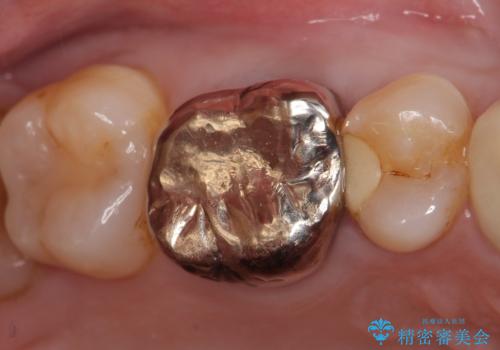

オールセラミッククラウン メタルフリーのクラウンへ

セラミックインレー 冷たいものがしみる奥歯の治療